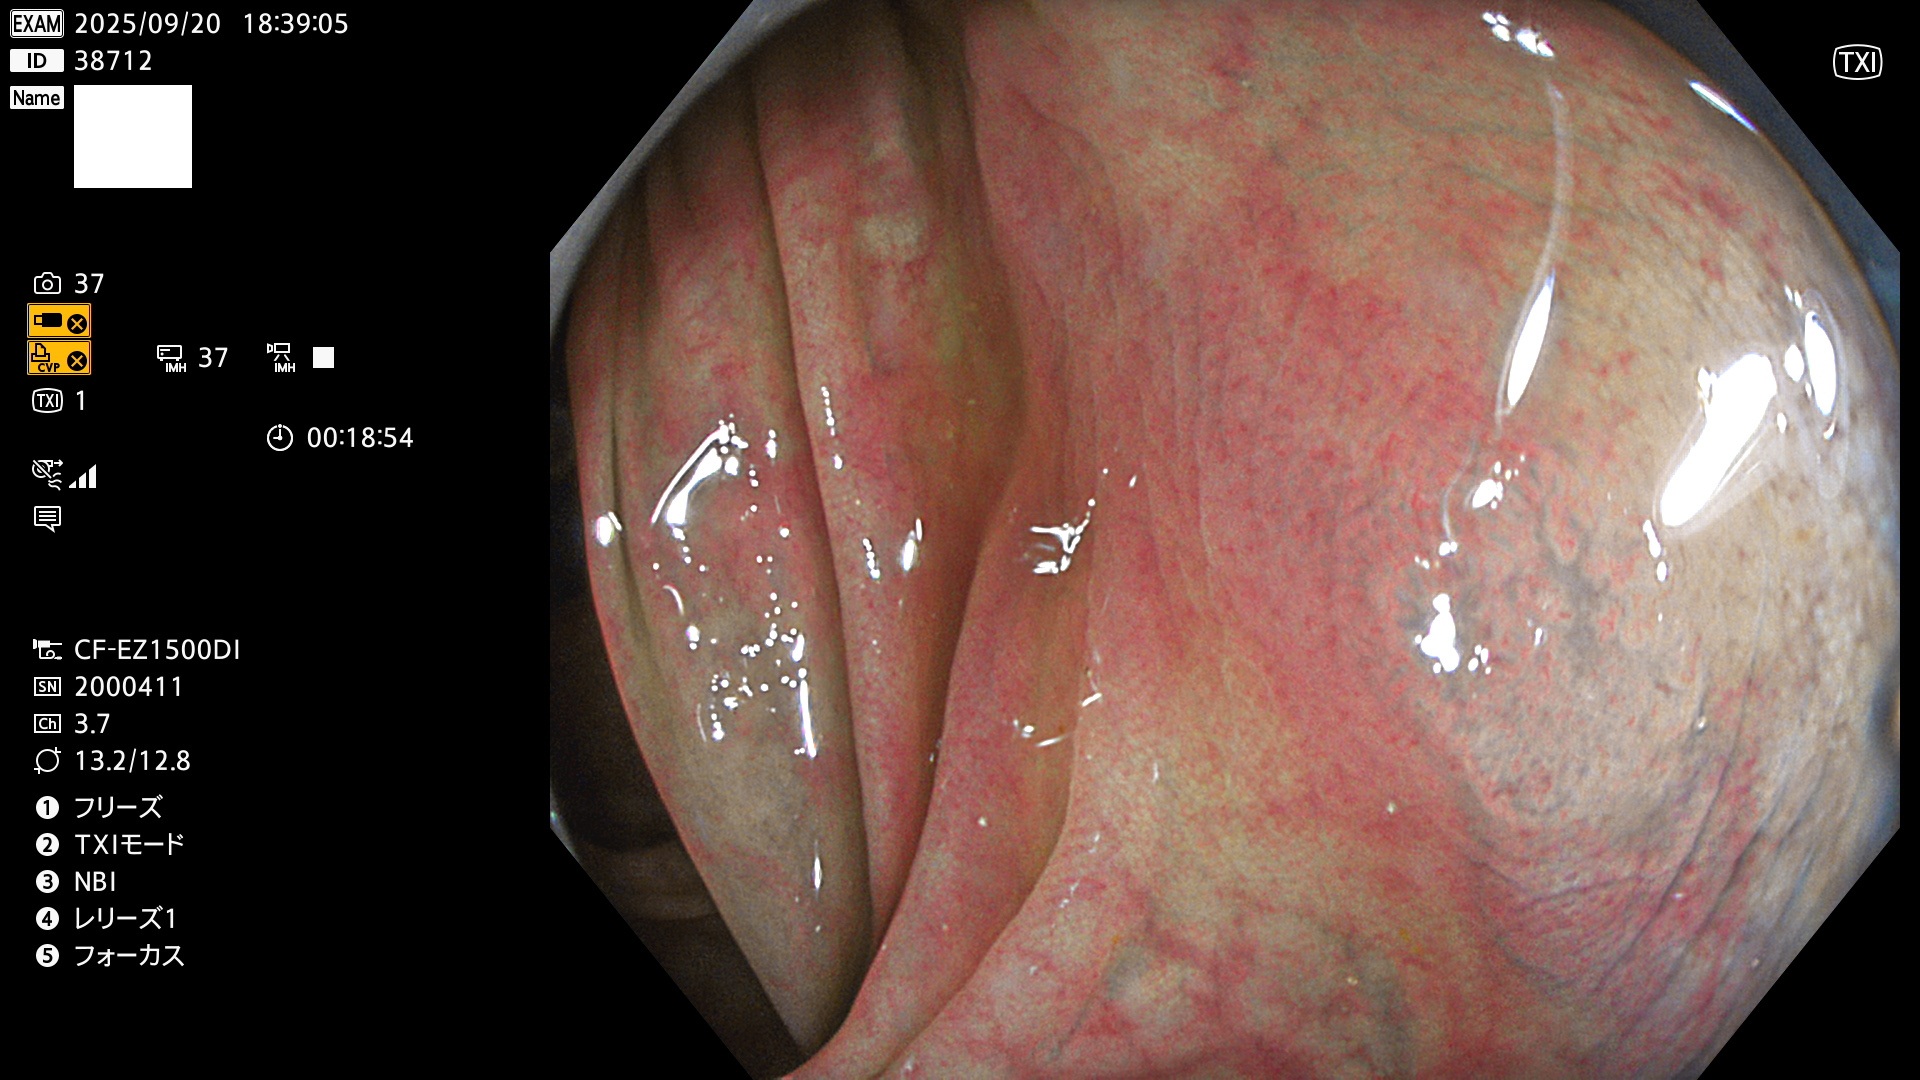

完全に平坦な物をUb、陥凹している物をUcと呼びます。Ubは認識が困難で、Ucはびらん(炎症)と紛らわしいために見落とされやすく、「内視鏡後・大腸癌」の原因になります。

毎週の検査(木・金・土・日)に発見されたUbとUc型・腺腫を、その週の日曜の夜にUPし1週間、提示します。

2025年9月17日〜9月21日の4日間(40件)6個 (Uc_ADR=6個/40人=15%)